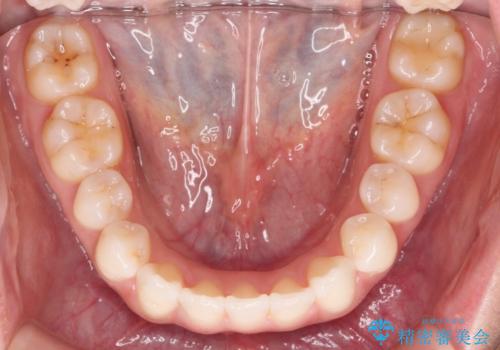

マイクロインプラントを用いてしっかりと後方移動を行ったことで前歯の角度は改善され、口元もすっきりと仕上げることができました。